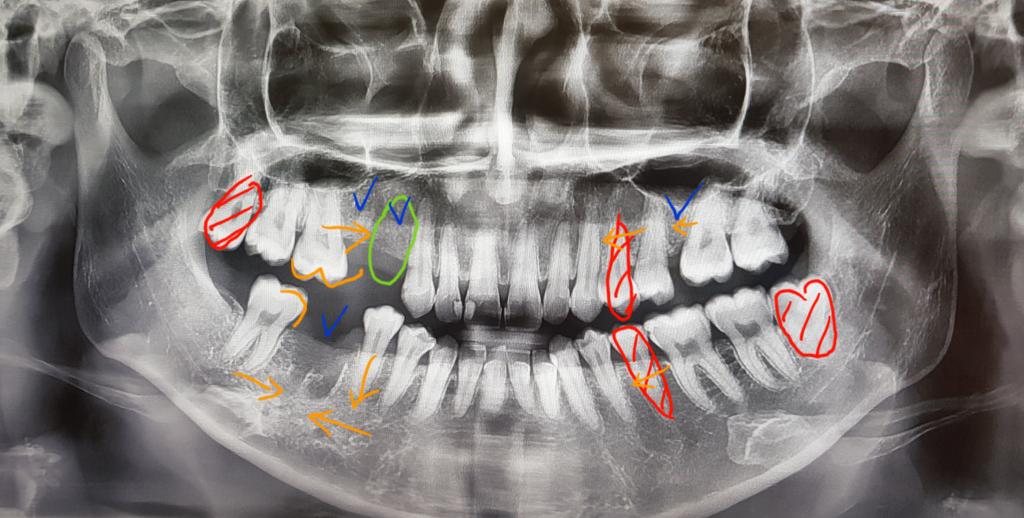

치아상태는 어렸을때부터 관리를 못해서 4개치아를 발치했어요..

파란색표시되어있는 부분이 치아를 발치한 자리구요

빨간색표시가 발치해야하는 치아입니다

연두색표시가 임플란트해야하는 곳이구요..

1. 첫번째 상담에선 위아래 5번째 치아 발치 후

임플란트 두개를 해야한다고 하셨어요

스크류도 왼쪽위쪽에 해야할수있다고 하셨구요

위에보단 아래가 많이 들어가 무턱에 효과를 크게 볼 수 있다고

하셨습니다..

2. 두번째 상담에선 위에 치아 4번, 아래치아 5번발치 후

임플란트는 하나만 하고 아래쪽 임플란트대신

작은 어금니랑 큰 어금니를 옮겨서 위에 큰 어금니 두개랑

교합을 맞춘다고 하셨어요..

임플란트 개수가 줄어들고 제 치아를 살릴수있어서 좋은방법같지만

어금니 하나만으로 과연 괜찮을까 나이먹어서 힘들진 않을까 걱정이 큽니다..

3. 세번째 상담에선 위엔 4번째 치아, 아랜 5번째 치아 발치 후

임플란트 두개 식립해야한다고 하셨어요

무턱이라 입이 최대로 들어가는 방법이라고 하셨지만

위에 4반째 치아를 발치하게 되면 5번치아 뒤에도 발치했던 곳이

치아가 무너져 약간 틈이 있는데 옥니처럼 너무 많이 입이 들어가는게 아닐지 걱정입니다

그리고 위랑 아래랑 다른 치아를 뽑아도 괜찮은지 걱정이구요..